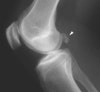

X-ray 소견은 대개 정상이지만, 간혹 낭종의 경계, 낭종 내 석회화 등이 보이기도 합니다.

X-ray : 베이커 낭종(슬와낭종, Baker's cyst, Popliteal cyst)